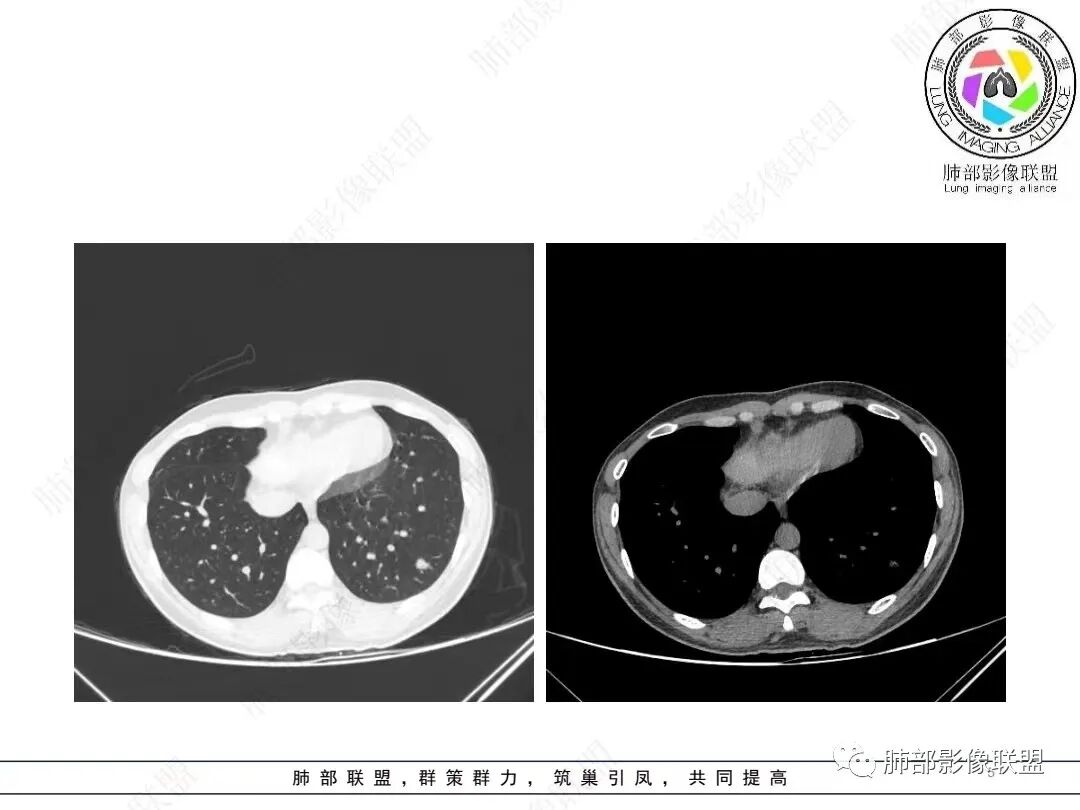

2、影像特点:左肺下叶类圆形结节影,周围可见多发细小毛刺,浅分叶,张力不高,未见胸膜牵拉。病灶内隐约见空泡影(未提供CT值),近端部分血管呈杵状增粗,可疑脐凹征。增强后实性部分有轻度强化。外围病灶,与支气管关系不明确。

年轻女性,体检发现,左肺下叶亚实性结节,边缘有毛刺、分叶,磨玻璃晕,病灶内可见裂隙样空腔改变,纵隔窗显示实性小于肺窗,近端血管呈杵状增粗,考虑腺癌,鉴别炎性结节(隐球菌),转移性结节。

年轻女性,无临床症状,肿标正常。影像左下肺孤立结节,周边毛刺,与血管相连,血管走形自然,部分层面似可见晕征,结节内多发空腔,腔内未见异常密度影,无钙化,考虑肉芽肿,隐球?鉴别:结核、肺癌